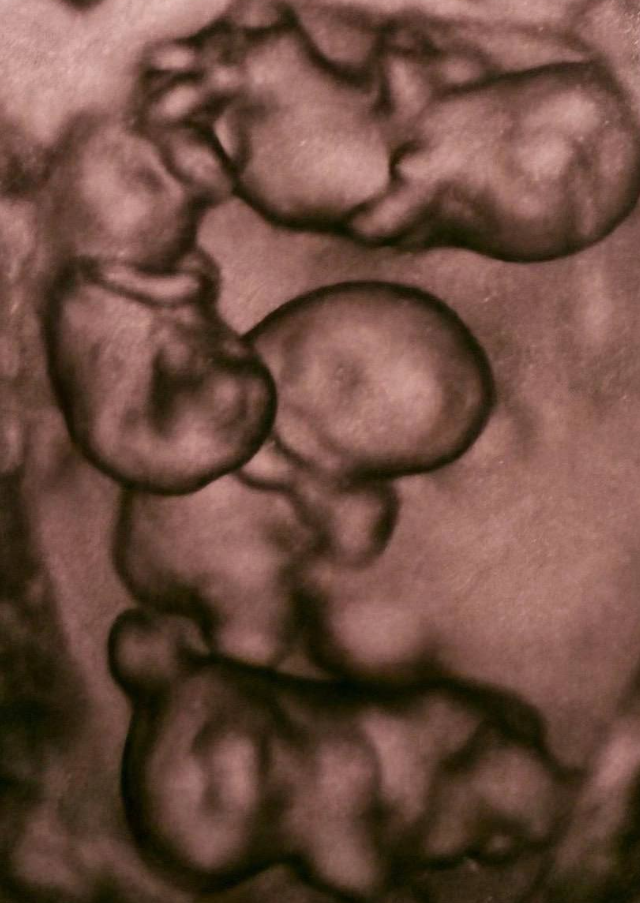

В Санкт-Петербурге зафиксирован уникальный для России случай - женщина родила однояйцевых четверняшек. Вероятность такого события оценивается примерно как один на 15,5 миллиона родов. На свет появились четыре полностью идентичные девочки, сейчас они находятся под наблюдением врачей. Подобные случаи крайне редки: во всём мире зарегистрировано около 15 таких рождений, и чаще всего это именно девочки. Рождение четверни считается событием экстра-класса, требующим слаженной работы большой медицинской команды.